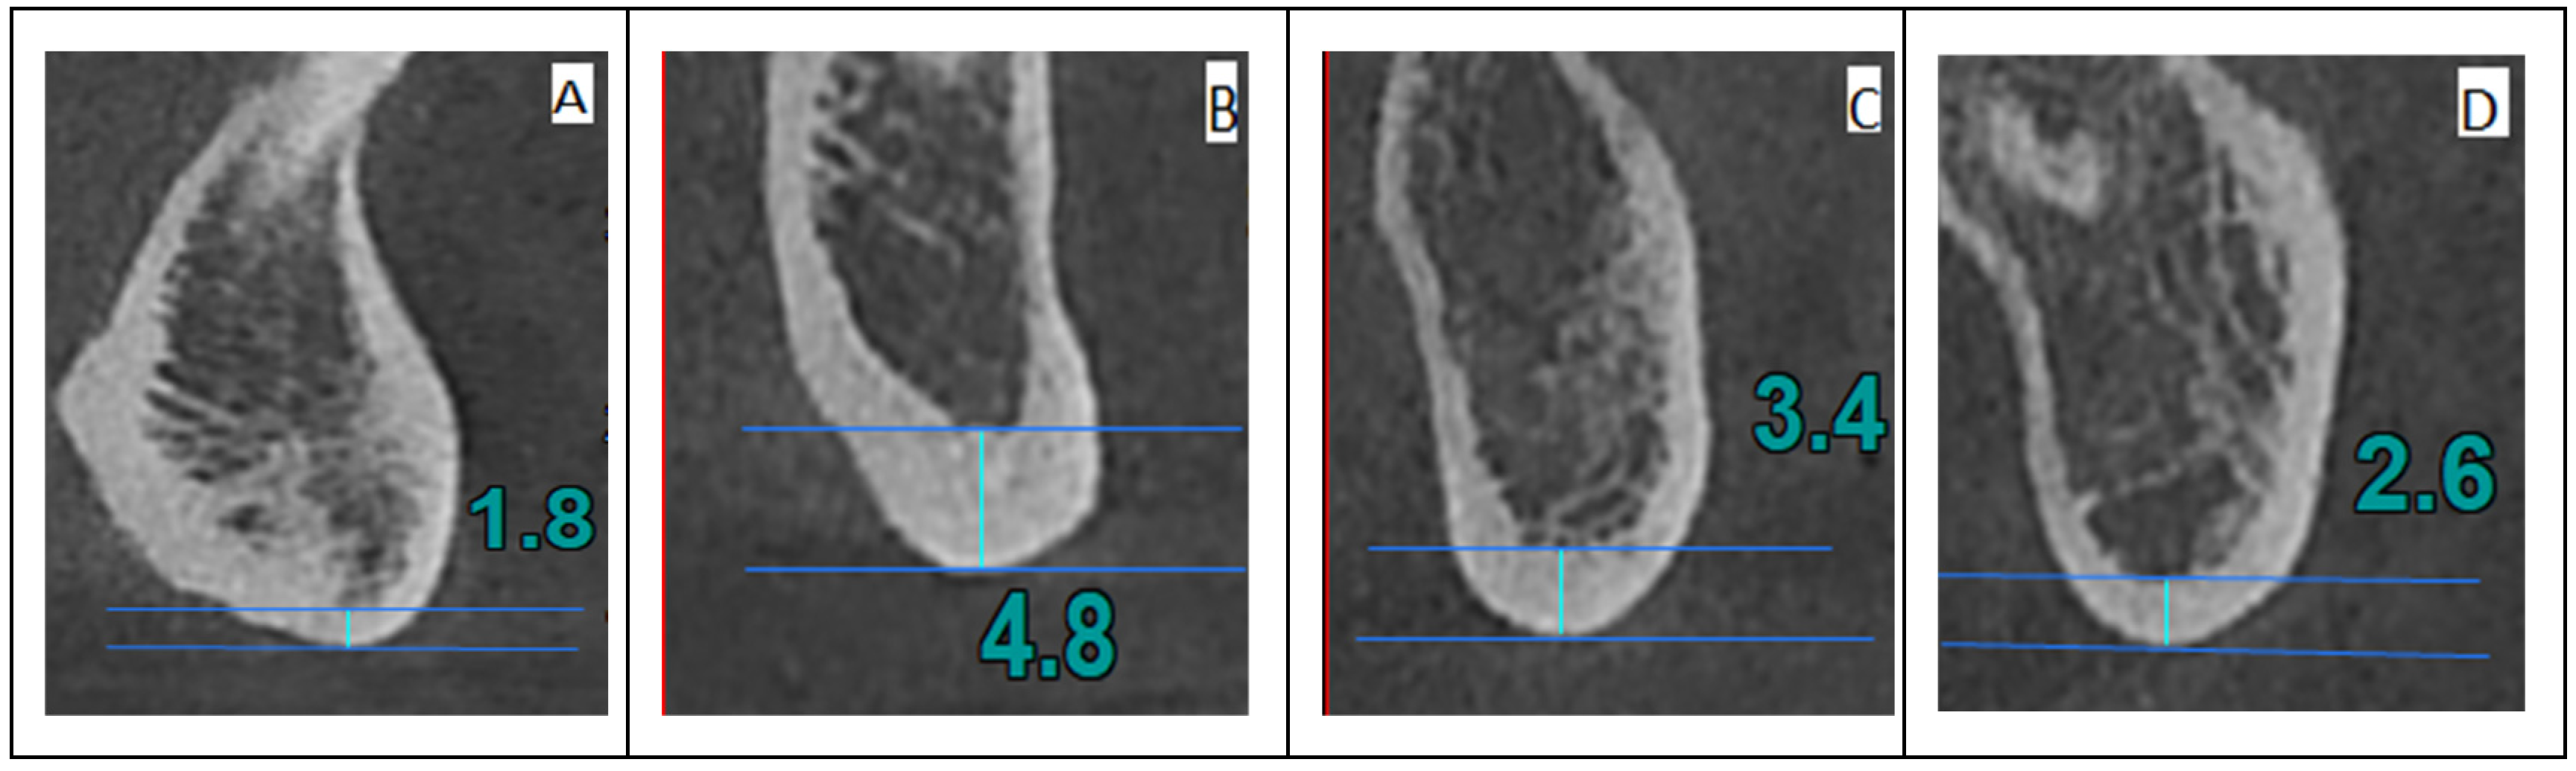

- Anterior index (A)—the thickness of the inferior mandibular cortex 10 mm anterior from the MF;

- Molar index (M)—the thickness of the inferior mandibular cortex 10 mm posterior from the MF;

- Posterior index (P)—the thickness of the inferior mandibular cortex 25 mm posterior from the MF;

- Symphysis index (S)—the thickness of the inferior mandibular cortex equidistant from the centers of the right and left MF.